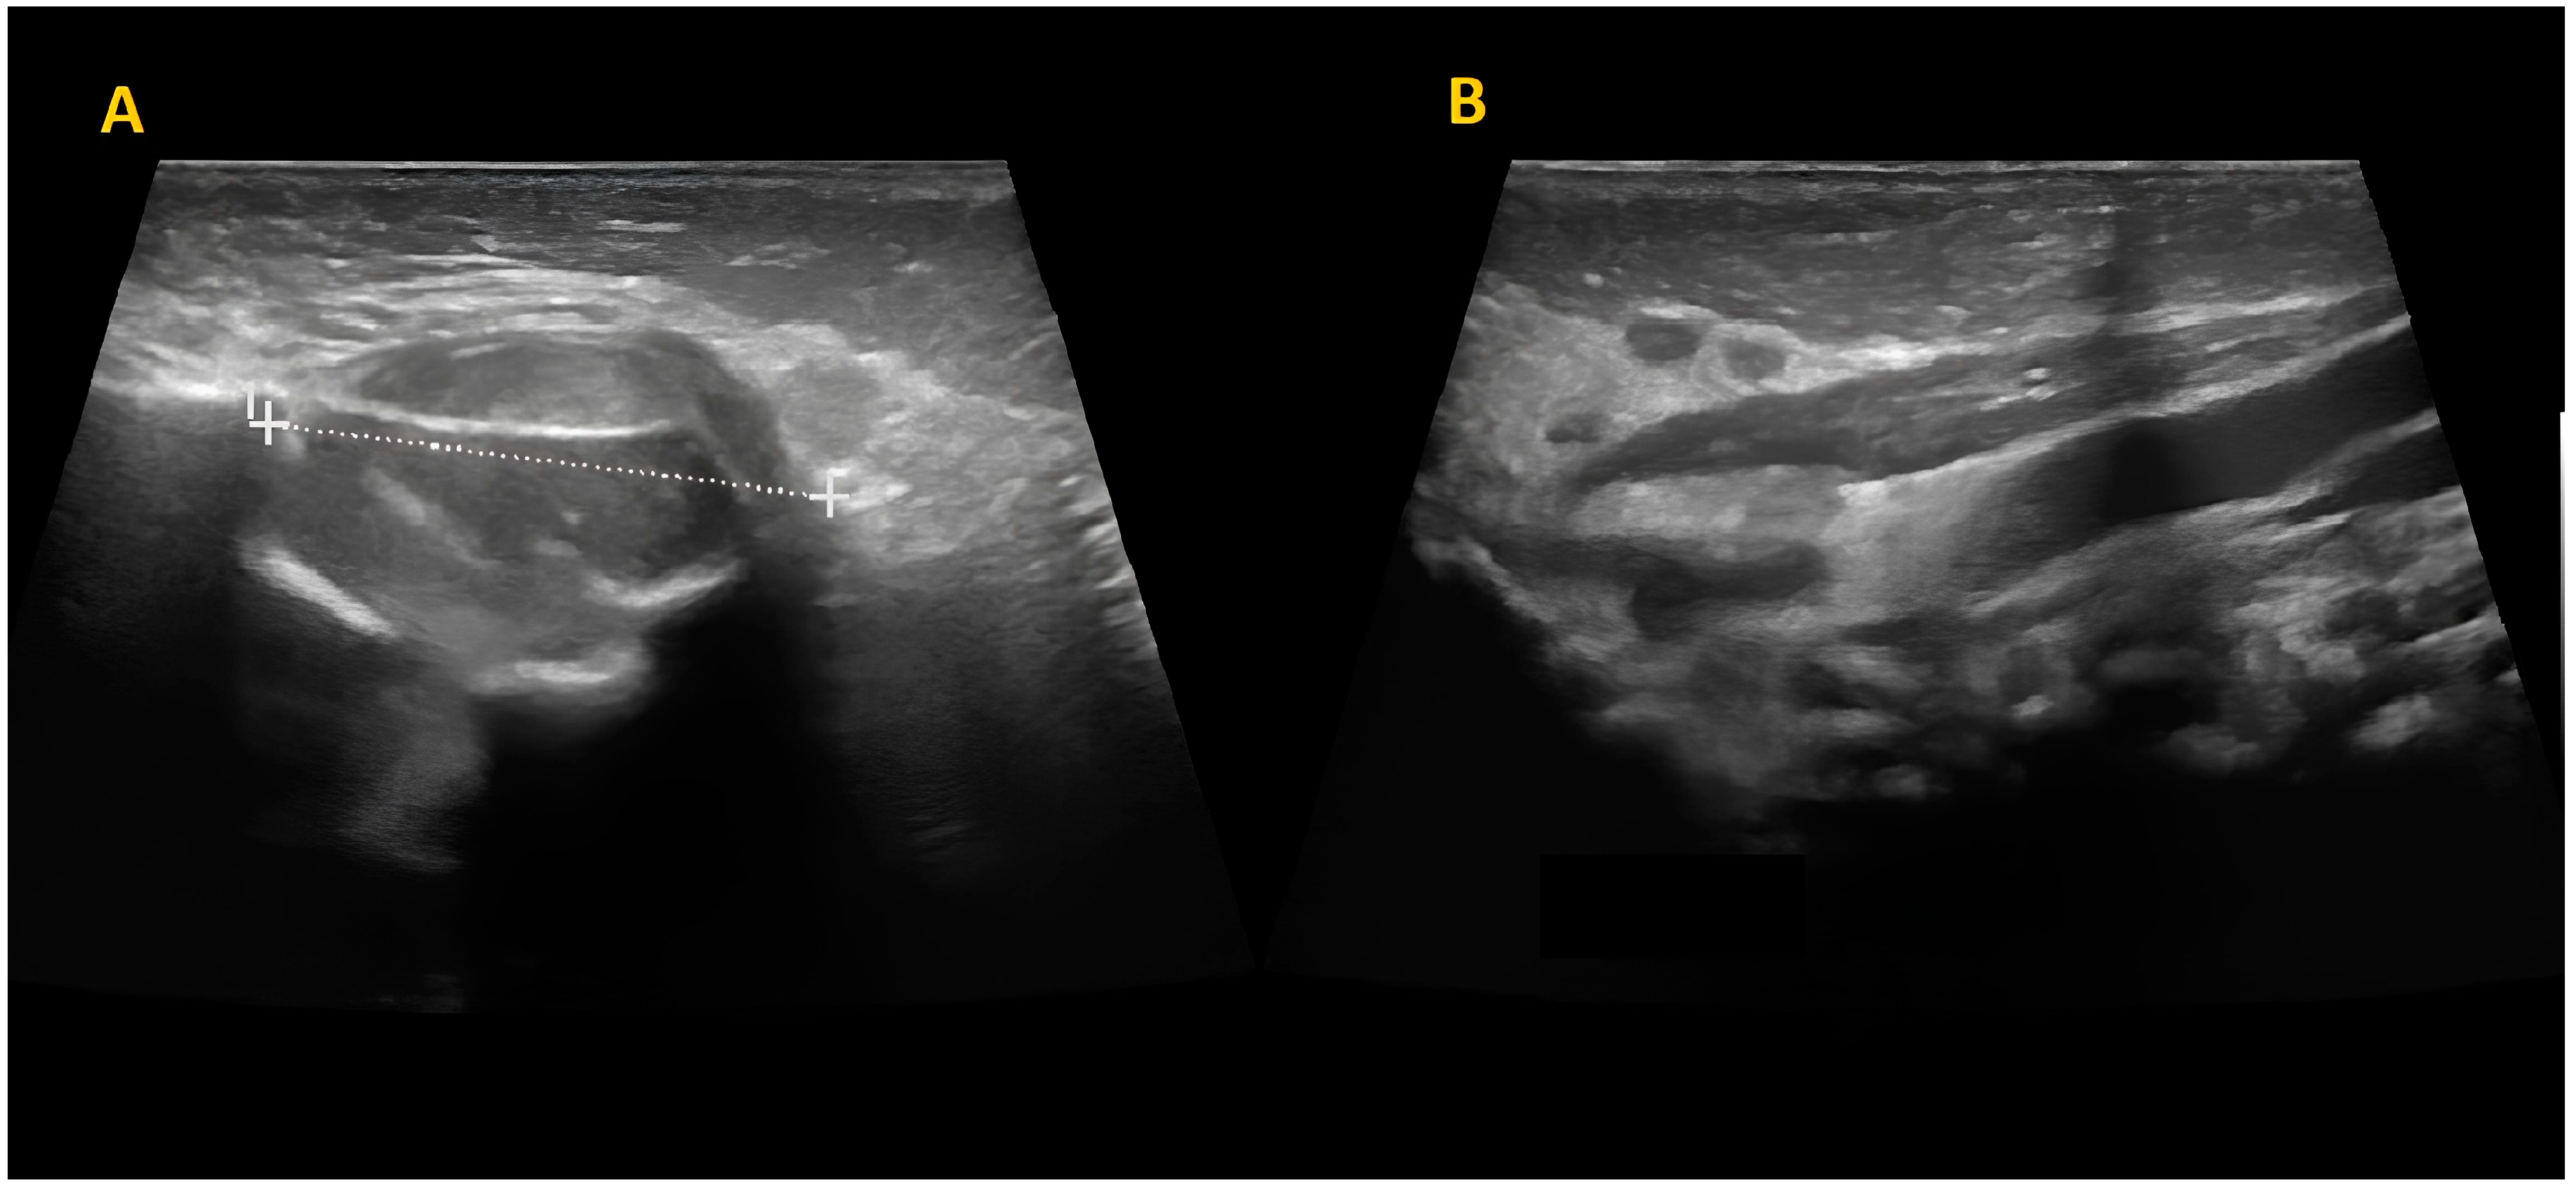

The mass was firm, partially mobile, cold, and apparently painless, with a diameter of around 2 cm. The lesion did not impair neck rotation and lateral movements, neither caused forced head position or tilting. An ultrasound study was performed and showed a fusiform mass over the left masseter muscle, which appeared inhomogeneous and hypoechogenic, sized 17 mm × 15 mm. The mastoid extremity of the homolateral sternocleidomastoid muscle (SCM) was also noted to be thickened (8 mm) (Figure 2).

Figure 2. Skin and subcutaneous ultrasound. A fusiform mass over the left masseter muscle, inhomogeneous and hypoechogenic, sized 17 mm × 15 mm (A). Concurrent thickening of the left sternocleidomastoid muscle at the mastoid head with increased thickness compared to the contralateral side (8 mm) (B).